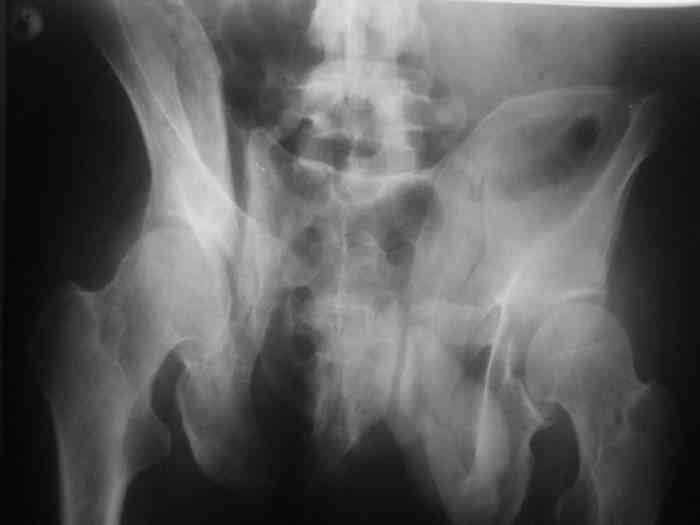

Остается только вариант закрытого аппаратного лечения. В аттаче положение отломков на вытяжении в прямой (АР) проекции. Для сравнения снимок до и во время вытяжения.

> Остается только вариант закрытого аппаратного лечения.. В аттаче

> положение отломков на вытяжении в прямой (АР) проекции. Для сравнения

> снимок до и во время вытяжения.

Только аппаратными методами в этом случае проблему не решить (фактически вы имеете дело с болтающимися псевдоартрозами), потребуется открытое вмешательство.

Первоочередно для тазовых операций важно обследование, снимки таза в инлет, оутлет и прямая

На сравнительном снимке правый полутаз опустился

недостаточно, можно добавить вес и сделать все стандартные снимки.